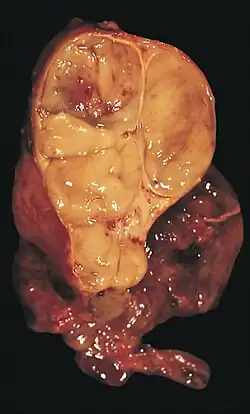

| An encapsulated thymoma (mixed lymphocytic and epithelial type) | |

A thymoma is a tumor originating from the epithelial cells of the thymus that is considered a rare neoplasm.[1] Thymomas are frequently associated with neuromuscular disorders such as myasthenia gravis;[2] thymoma is found in 20% of patients with myasthenia gravis.[3] Once diagnosed, thymomas may be removed surgically. In the rare case of a malignant tumor, radiation therapy may be used.